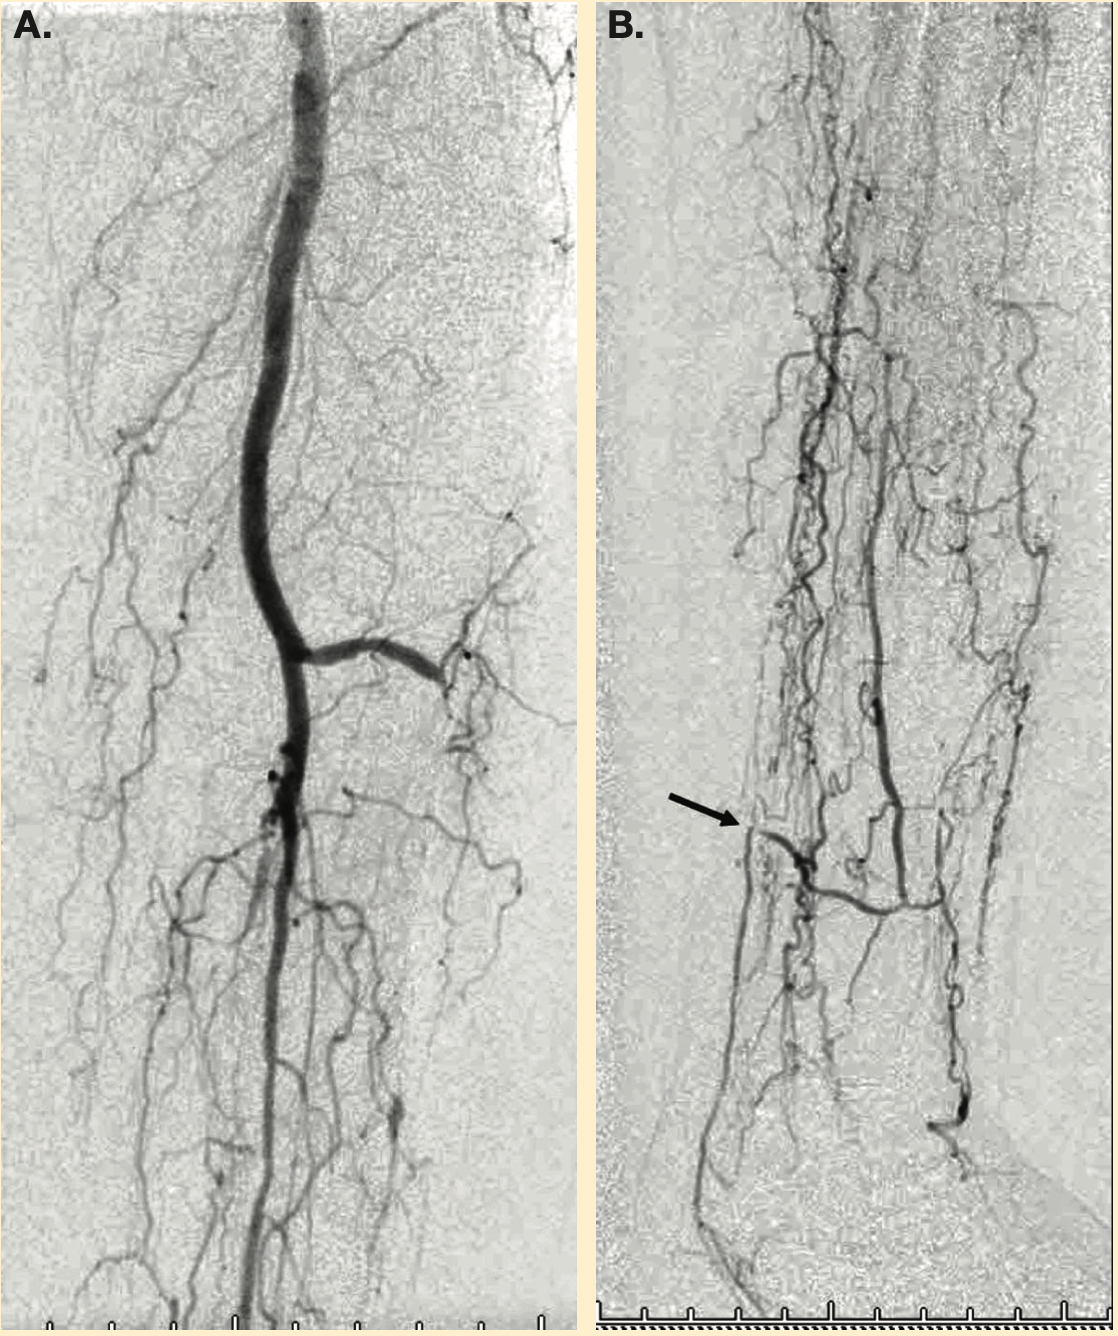

This is an 81-year-old female with a 5-week history of left heel ulceration. Her past medical history includes diabetes mellitus, hypertension, chronic kidney disease stage IV, and dyslipidemia. She is status post right above-knee amputation. Physical exam revealed palpable femoral pulses and no distal pulses in the left foot. Left ankle-brachial index (posterior tibial artery) was 0.36.